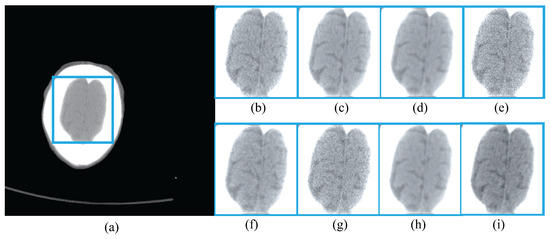

4.4. Head Dataset